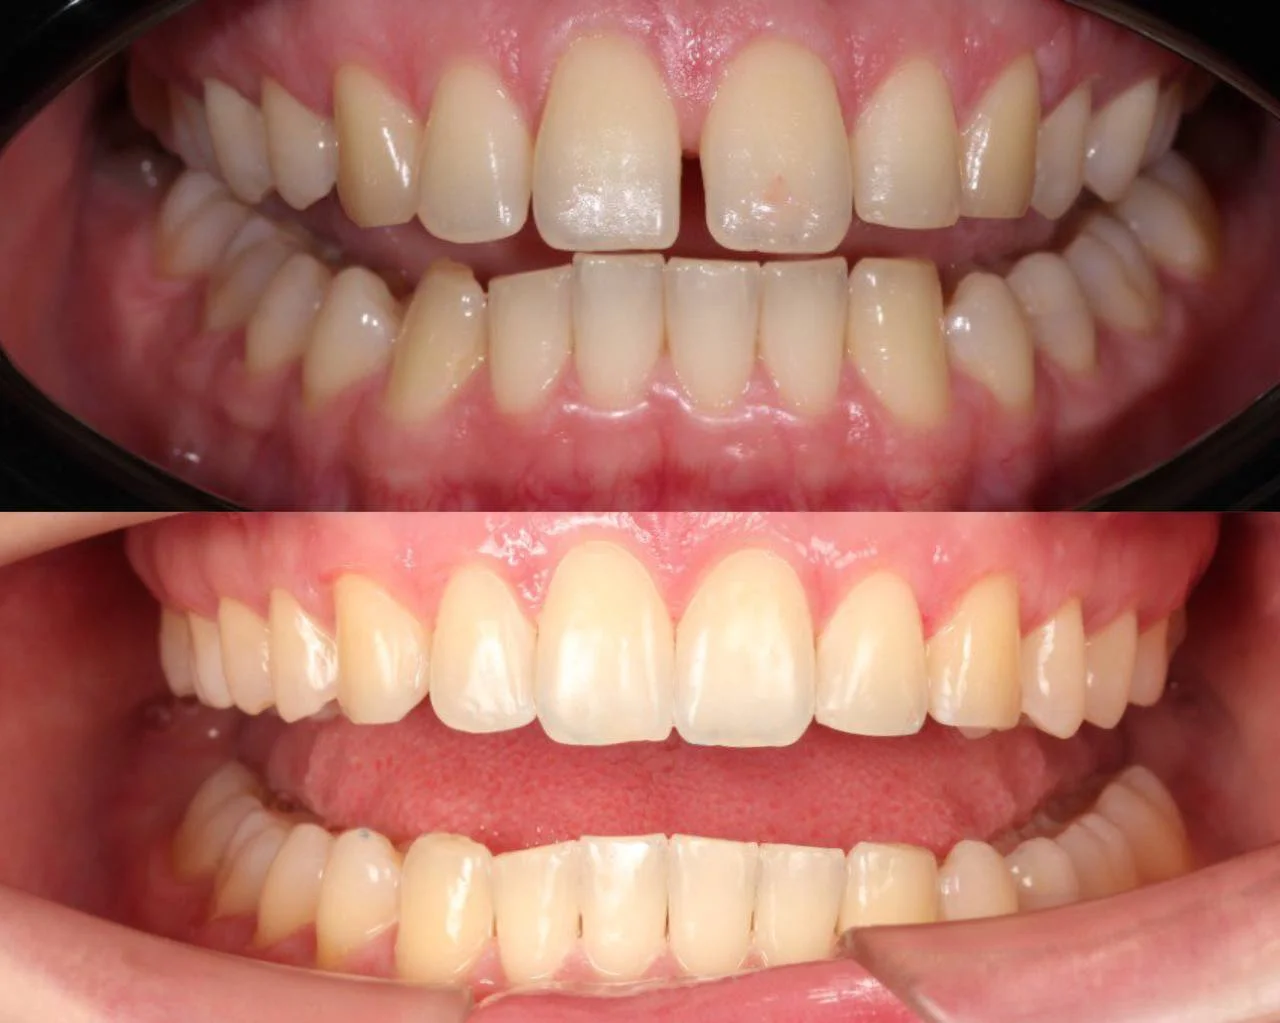

Нарушение соотношения челюстей и неправильное положение зубов — зубные ряды смыкались некорректно, зубы стояли со смещением.

Прозрачные элайнеры 3D Smile на обе челюсти. Выровнять зубы и нормализовать смыкание. Основной набор — 34 капы. Срок — около 2 лет.

Лечение заняло 32 месяца (февраль 2023 — октябрь 2025). Понадобился один дополнительный набор из 28 кап — итого 62 капы. Параллельно проводилась профессиональная гигиена.

Зубы выровнены, смыкание нормализовано. Установлены несъёмные ретейнеры на обе челюсти, сняты сканы для ретенционных кап. Консультация ортопеда запланирована на более поздний срок.

Проблема: Пациентку беспокоило неправильное смыкание зубов и их положение — ряды не сходились как нужно, зубы стояли со смещением. Это влияло и на внешний вид, и на то, как распределялась нагрузка при жевании.

Решение: Поставили прозрачные элайнеры 3D Smile на обе челюсти. Начали с набора из 34 кап, но в процессе стало понятно, что для полной коррекции нужна доработка — заказали дополнительный набор из 28 кап. Это нормальная ситуация: организм реагирует на перемещение зубов индивидуально, и заранее предсказать точное количество кап до последней штуки невозможно. В итоге 62 капы за 32 месяца — зубы встали на место, смыкание пришло в норму. Параллельно следили за гигиеной, чтобы дёсны оставались здоровыми на протяжении всего лечения.

Основной набор из 34 кап выполнил бо́льшую часть работы, но для финальной коррекции смыкания понадобился дополнительный комплект. Это не редкость — зубы двигаются с разной скоростью, и последние доли миллиметра часто требуют доработки. В итоге получили стабильный результат, который зафиксировали ретейнерами.